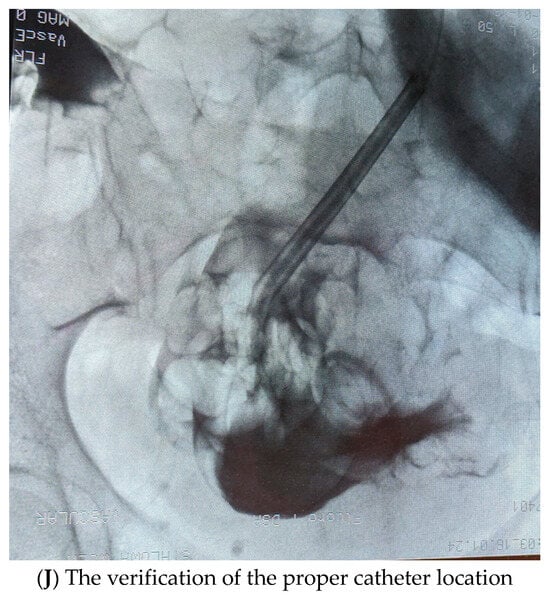

- The coiled catheter was then placed on the stylet (double-cuff Tenckhoff coiled catheter—Covidien, Mansfield, MA, USA), advanced through the sheath to the peritoneal cavity (Figure 1I). The catheter tip is placed deeply into the recto-vesical space in men and the recto-uterine space in women, which is the most gravity-dependent region where dialysate fluid accumulates, potentially providing the best drainage of dialysis fluid. To verify the proper location, the fluoroscopic location was used (Figure 1J). The internal catheter cuff was placed next to fascia. Next, a catheter flow test was performed to check the catheter function (300–500 mL of peritoneal fluid was administered and drained).